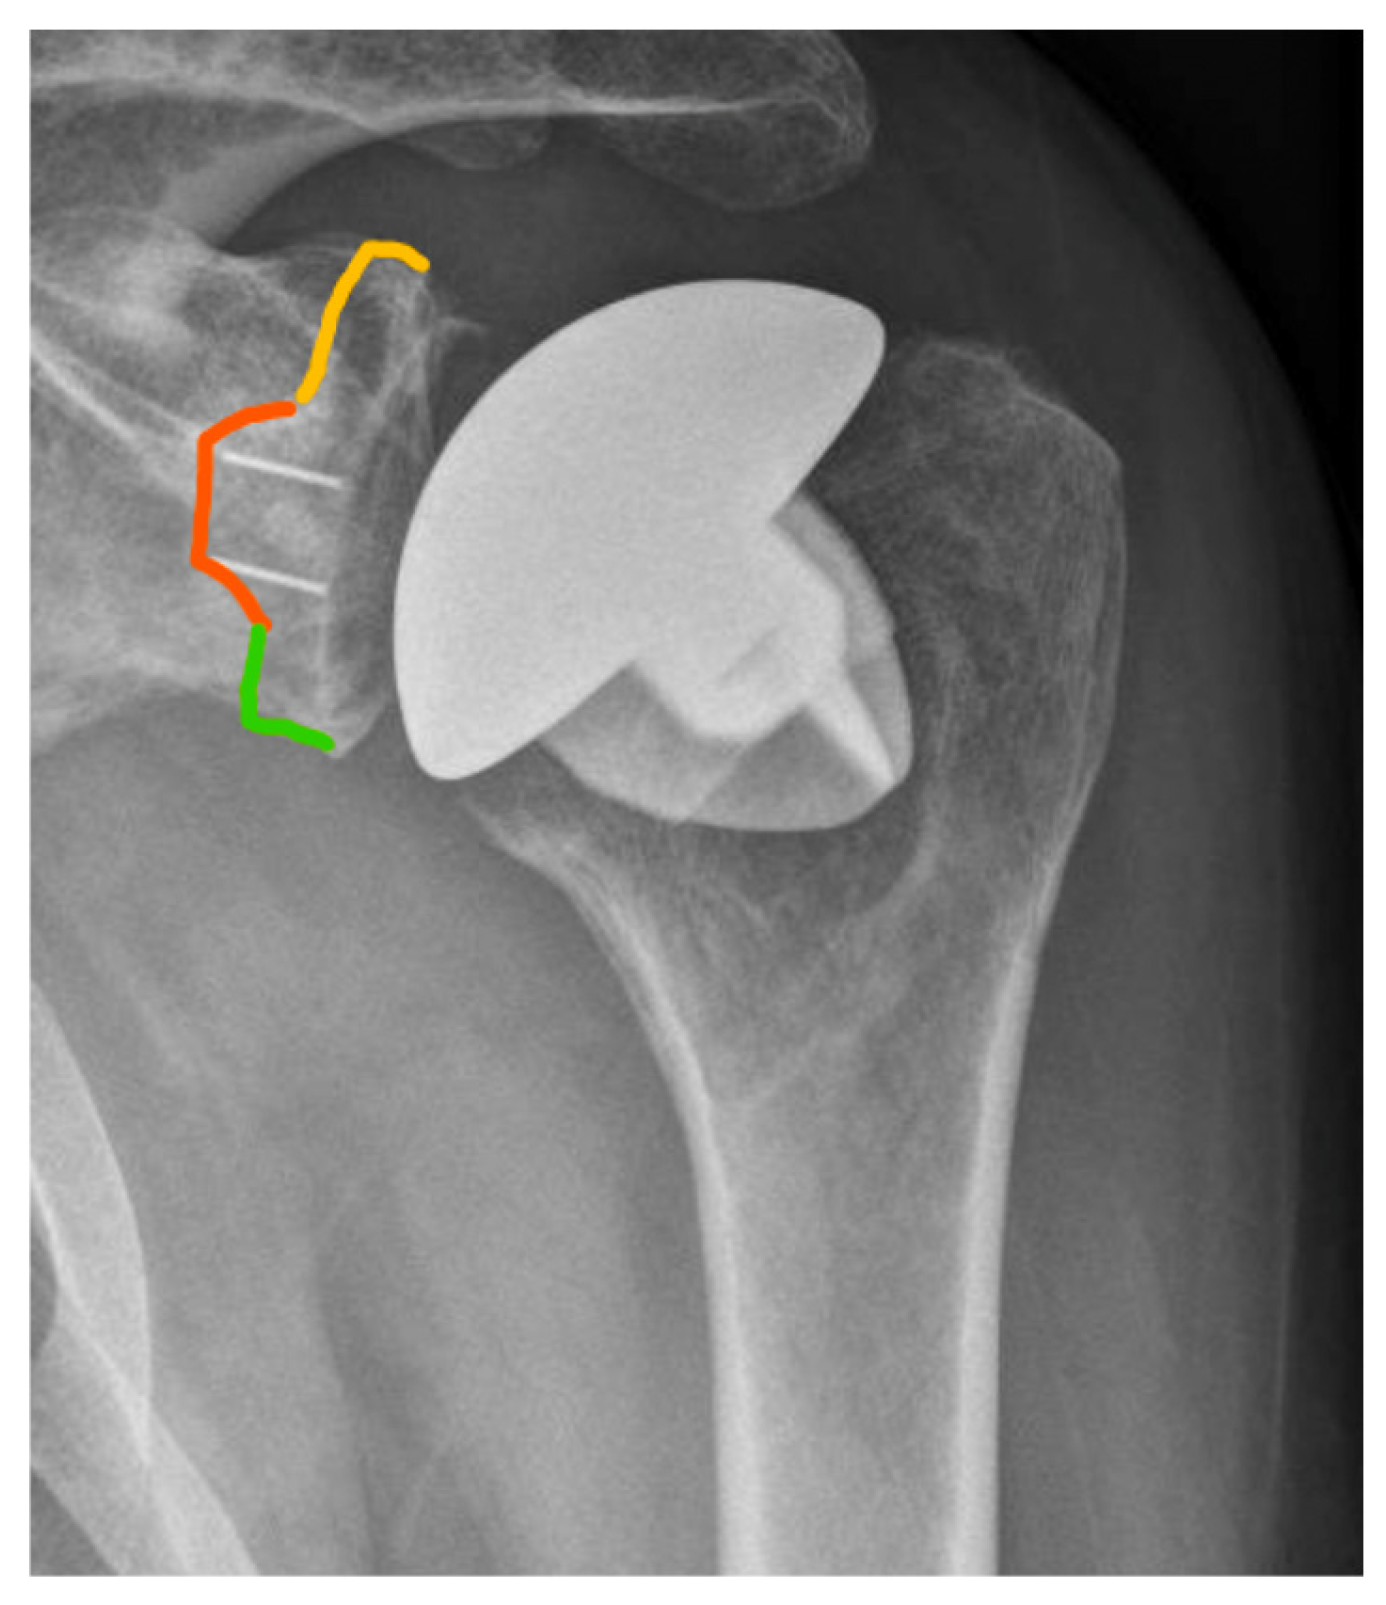

2.4. Radiographic Assessment